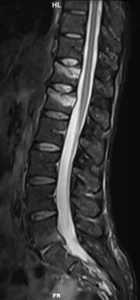

Resonancia Magnetica

RM sagital en secuencias T2 (1), T1 (2) y STIR (3). La RM permite establecer qué se trata de un trauma reciente por la presencia de edema óseo (hiperintenso en secuencias ponderadas en T2, hipointenso en T1). Es el método de elección para evaluar la médula espinal, el cono y las raíces nerviosas. Adicionalmente, muestra la patología degenerativa discal y vertebral.

Qué agrega la RM (y cuándo es clave):

- Confirma edema medular óseo (fractura aguda) y ayuda a diferenciar fracturas recientes vs crónicas.

- Valora lesión ligamentaria (complejo posterior) y tejidos blandos paravertebrales.

- Evalúa médula/conus/cauda y hematoma epidural si hay síntomas neurológicos.